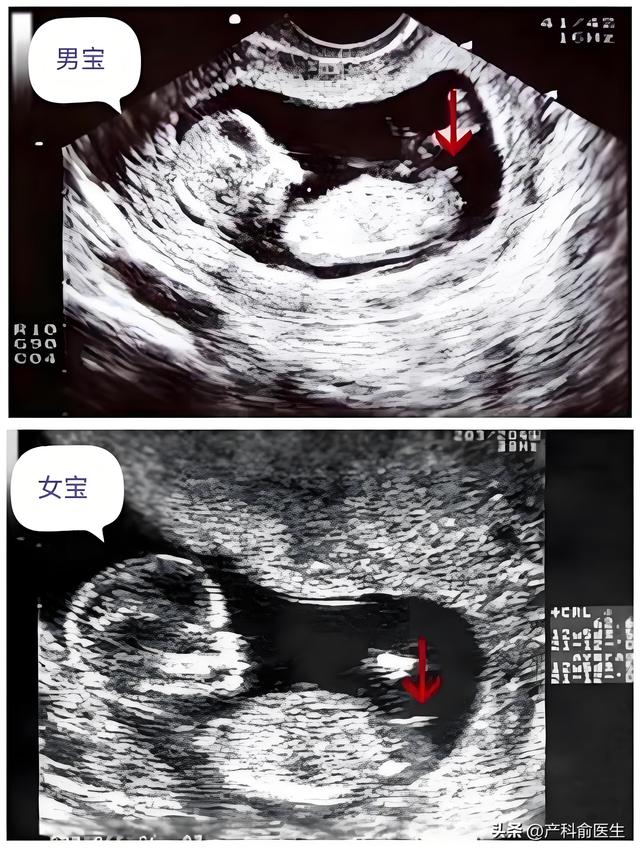

看数值:声称NT值高是男孩,低是女孩。看图像:认为B超图中胎儿姿势或脊柱角度能暗示性别。

这些说法其实都缺乏科学依据。医学研究表明,NT值与胎儿性别之间没有统计学关联。曾有学者对5000多例NT数据进行分析,发现男女胎儿的NT平均值差异仅为0.02毫米,远低于测量误差范围。至于B超图像判断,更属于主观臆测——胎儿在子宫内的姿势千变万化,与性别毫无关联。